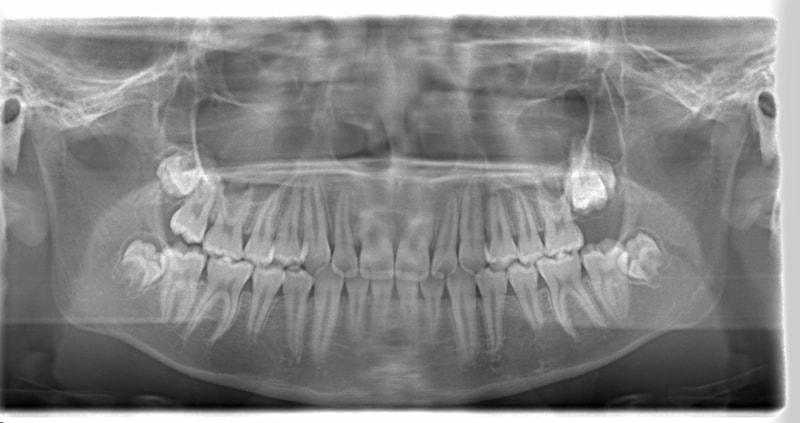

FX(フェイシャルアキシス)は85度なので東洋人の平均値に近く、下顎が前方に過剰成長するリスクは強くはありません。

しかしやはり上顎は劣成長で、下顎が優位な状態ではあります。

上下顎のギャップはありますが、顔面自体の幅径は良好な値を示していますので、スペース不足は拡大することによって解決できポテンシャルはあると考えられます。

左右の非対称もさほど強くありません。

骨年齢は実年齢よりも低めなので、今後下顎の旺盛な成長が見込まれます。

検査時のレントゲン分析では、上下顎の関係は、上顎の劣成長があり下顎前突傾向という値がでておりましたが、前歯ジャンプ後はフェイスマスクの効果もあり、上下顎の関係は正常化しています。

上顎が若干優位になっていますので、今後の下顎の成長のための貯金になっているくらいです。